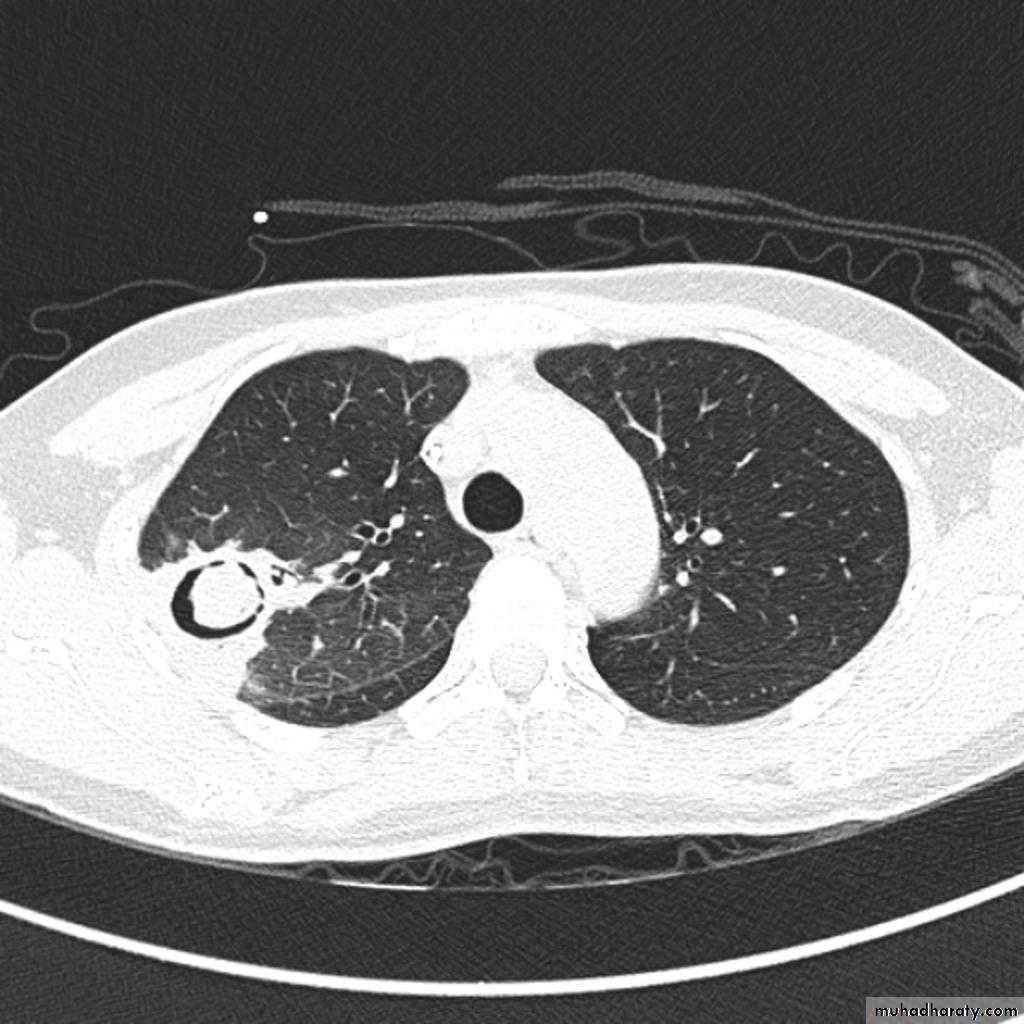

Pulmonary emphysema is defined as the "abnormal permanent enlargement of the airspaces distal to the terminal bronchioles accompanied by destruction of the alveolar wall and without obvious fibrosis". Emphysema is one of the entities grouped together as chronic obstructive pulmonary diseaseRadiographic features

Plain filmExcept in the case of very advanced disease with bulla formation, chest radiography does not image emphysema directly, but rather infers the diagnosis due to associated features :

hyperinflation:

1.flattened hemidiaphragm(s): most reliable sign

2.ncreased and usually irregular radiolucency of the lungs

9.vascular changes paucity of blood vessels ( absent pulmonary markings in outer 1/3 of the lung fields )